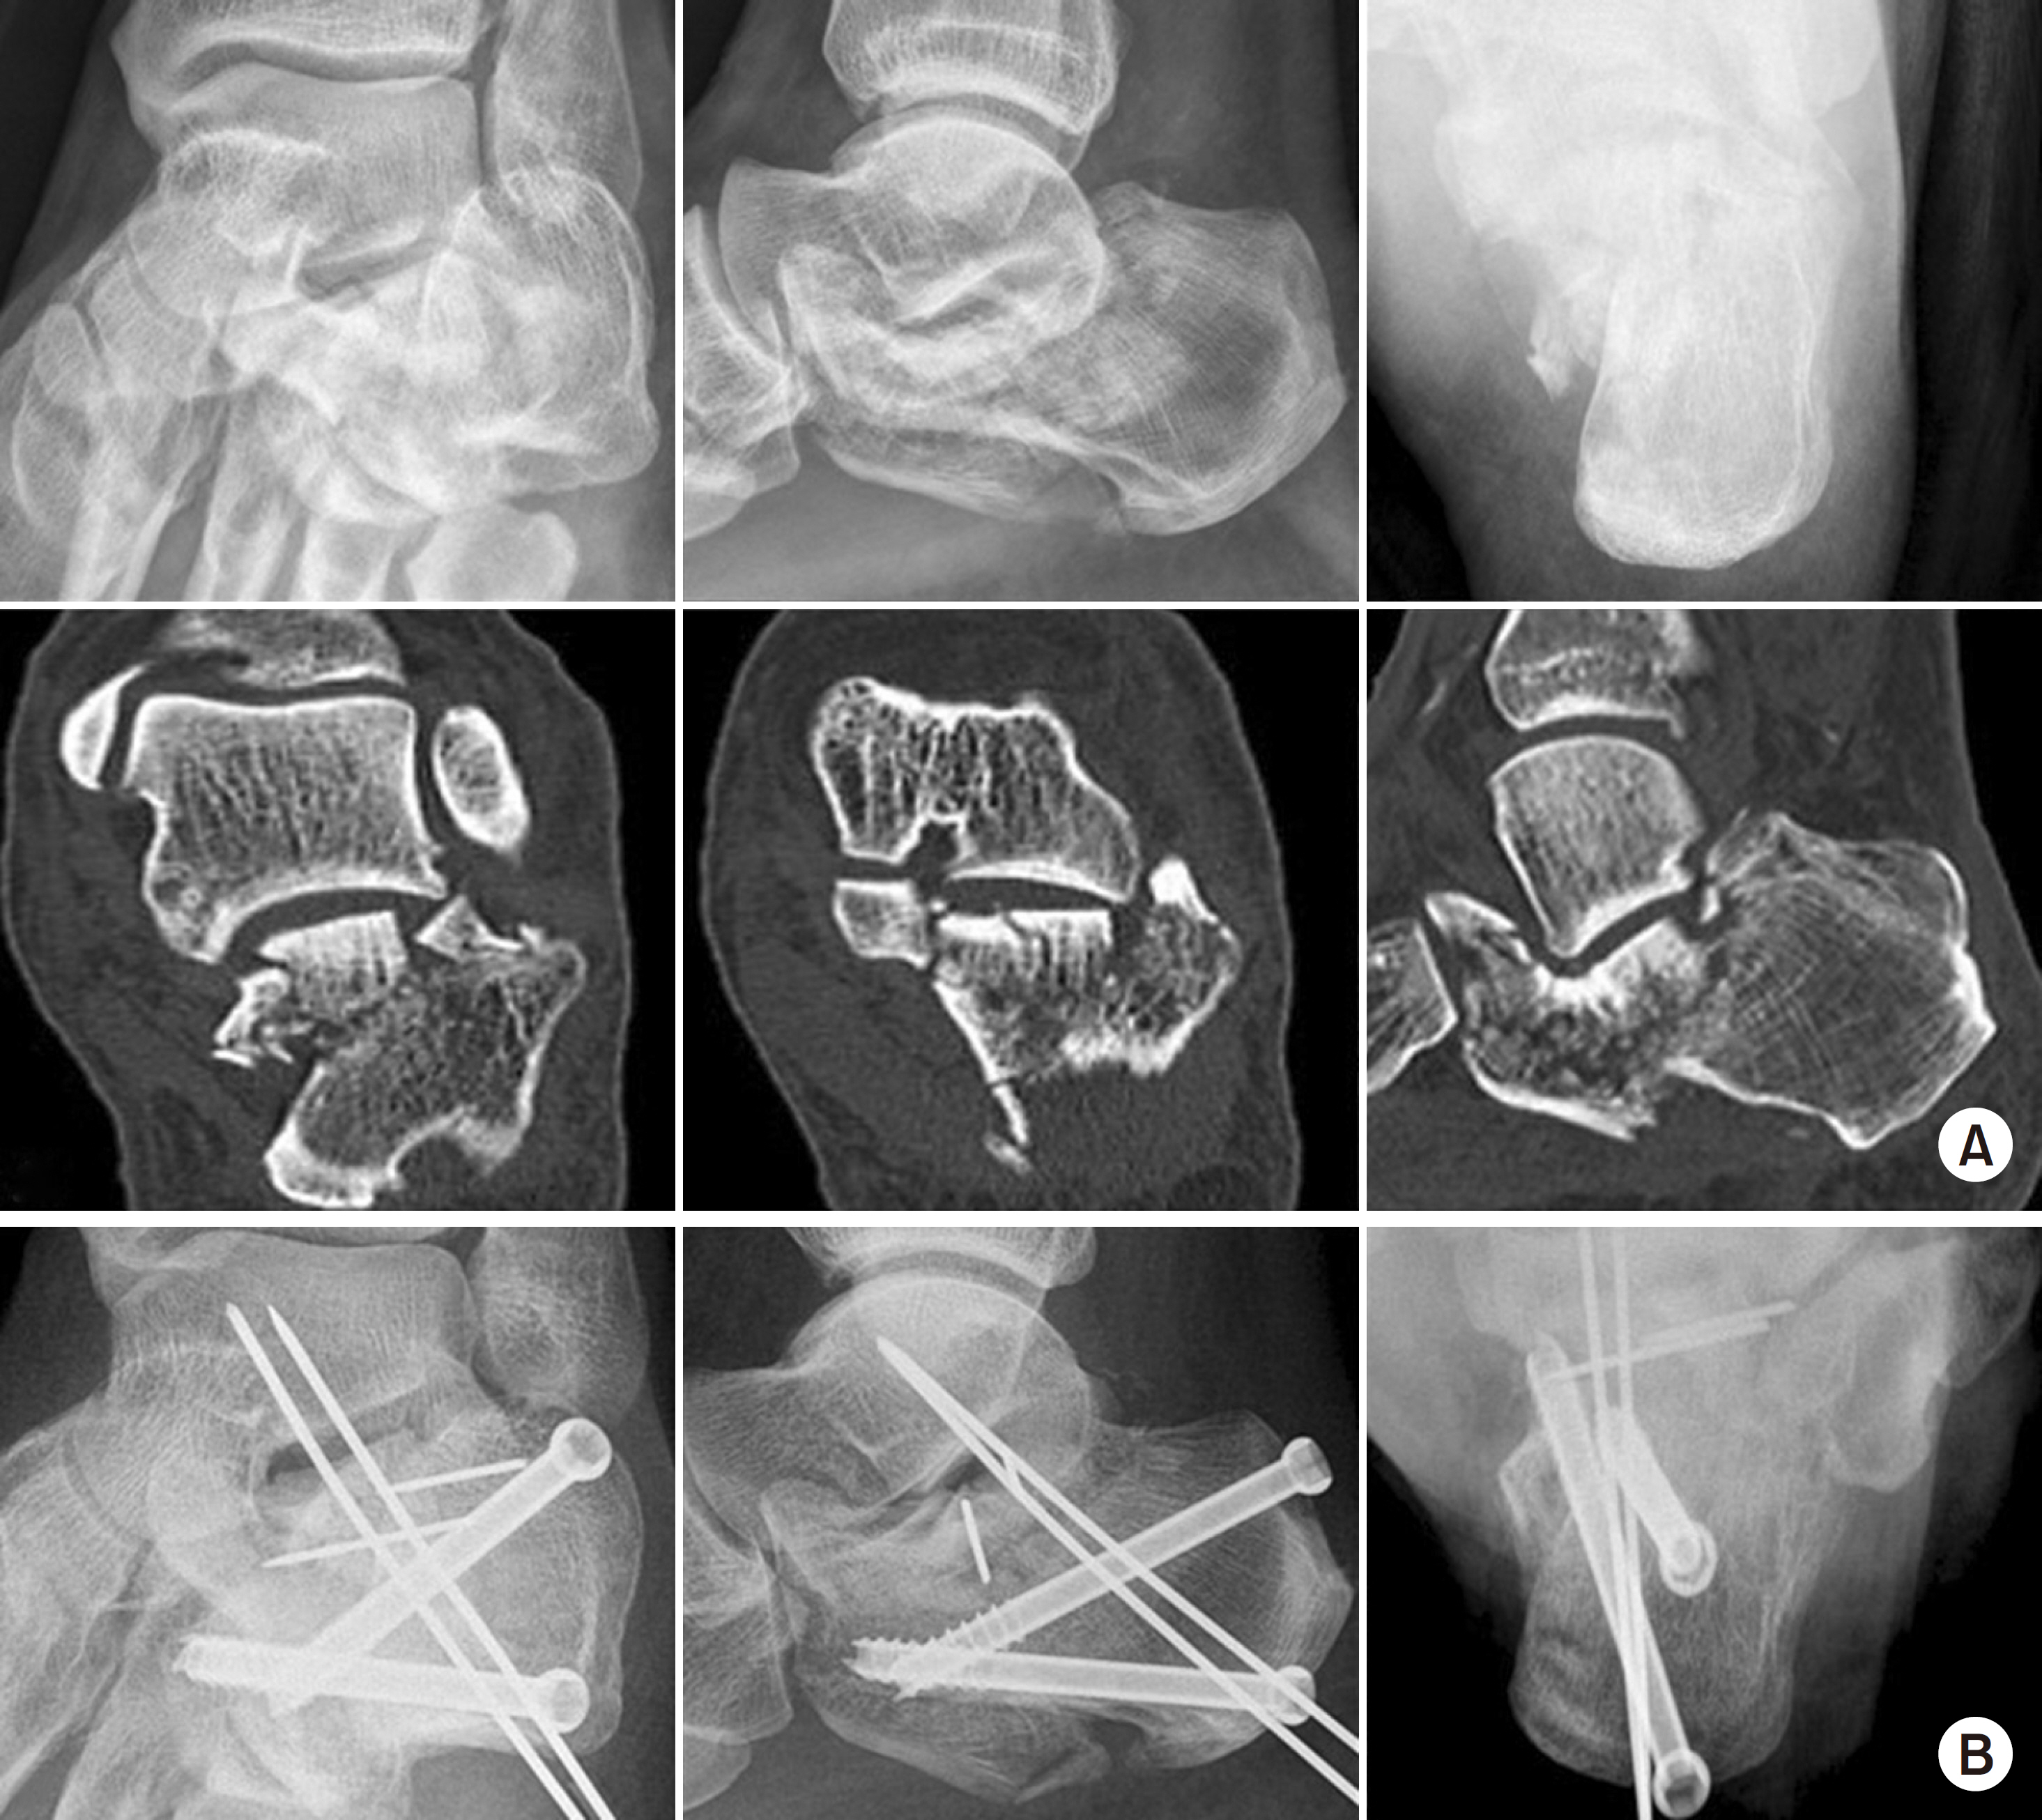

Fig. 3.

Intraoperative fluoroscope images showing posterior facet reduction using Schantz pin and fixation with 6.5 mm cannulated screws and K-wire.